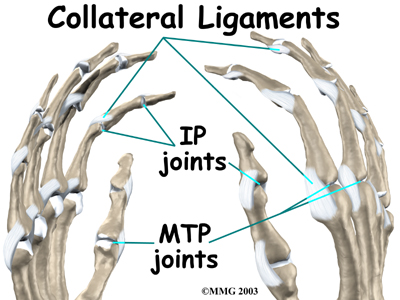

Ligaments are tough bands of tissue that connect bones together. Two important structures, called , are found on either side of each finger and thumb joint. The function of the collateral ligaments is to prevent abnormal sideways bending of each joint.